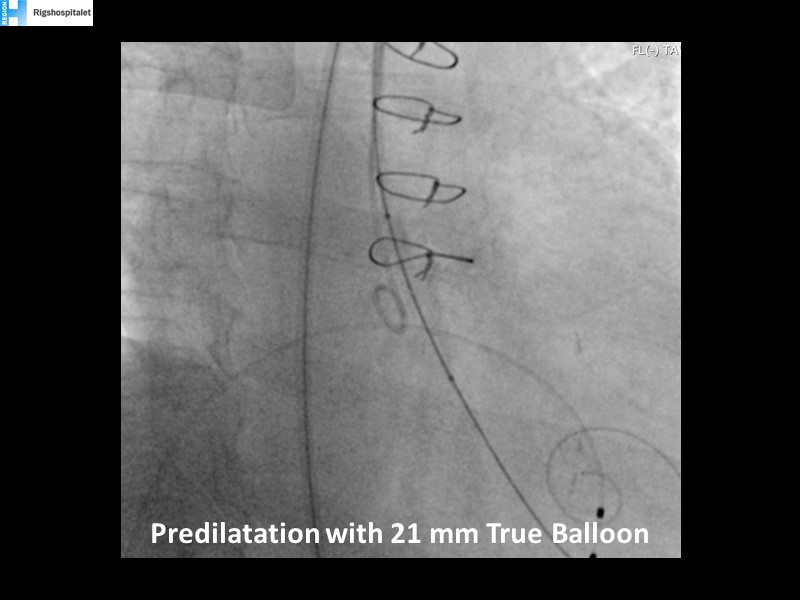

Your most challenging TAVI cases - Achieving precision and control with Evolut platform

How to deal with challenging anatomies? Find answers in this EuroPCR 2022 session with case studies to explore and learn how to achieve optimal patient outcomes with Evolut platform, uncover practical tips and techniques to achieve implant precision and control, and become familiar with technical considerations and procedural execution of TAVI.

- To learn how to achieve optimal patient outcomes with Evolut platform in diverse challenging anatomies

- To uncover practical tips and techniques to achieve implant precision and control

- To become familiar with technical considerations and procedural execution of TAVI